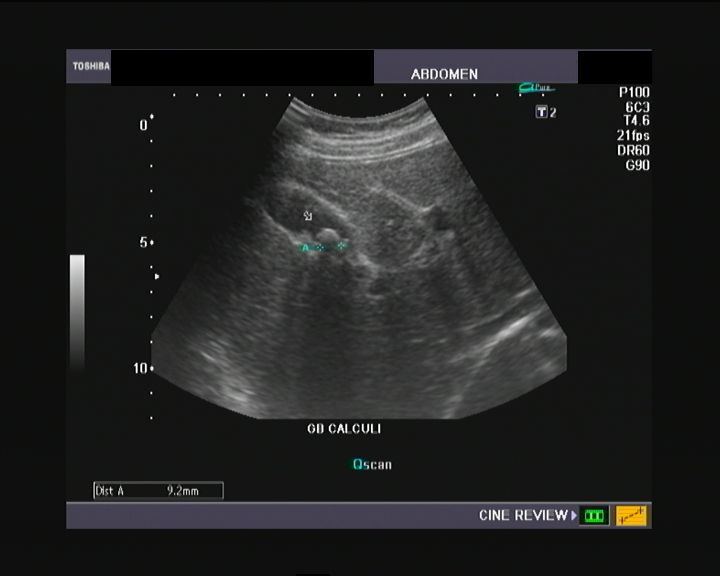

From www.wikidoc.org

Kidney stone ultrasonography wikidoc Fused Pelvic Kidney Ultrasound pancake kidney (also known as discoid kidney, disc kidney, lump kidney, fused pelvic kidney or cake kidney) is a rare renal fusion anomaly. this index case of a rare combination of bilateral laterally rotated, posteriorly fused, ectopic pelvic kidneys. instead of being a defect of only one kidney, both kidneys are fused, forming one single u shaped. Fused Pelvic Kidney Ultrasound.